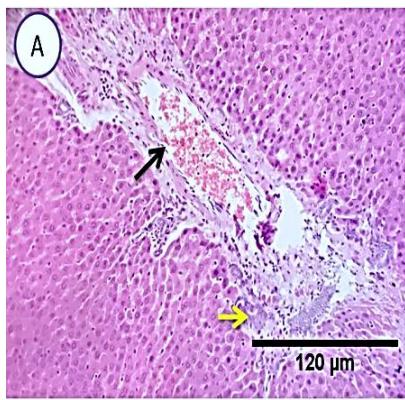

Liver: Sections from liver of this group denoted moderate portal biliary proliferation, congestion of portal blood vessels, round cell infiltration, multifocal interstitial lymphocytic and macrophages aggregations replacing previous necrotic patches beside degenerative changes in a few hepatocytes. (Fig.10)

Fig. 4: Photo-micrograph from liver, group (4), showing, portal biliary proliferation (A, yellow arrow, B, black arrow), congestions of portal blood vessels(A, black arrow), round cell infiltration and interstitial lymphocytic and macrophages aggregations replacing previous necrotic patches (B, blue arrow). Scale bars 120, 40, 40 um.